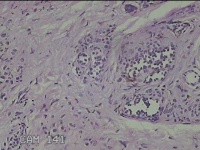

头部新生物

性别

男

年龄

31岁

临床诊断

纤维瘤

一般病史

头部皮肤起新生物1年。

标本名称

大体所见

灰白粉红色新生物1.7x0.5x0.3cm一个,表面糜烂,肿物表面有大量毛发。